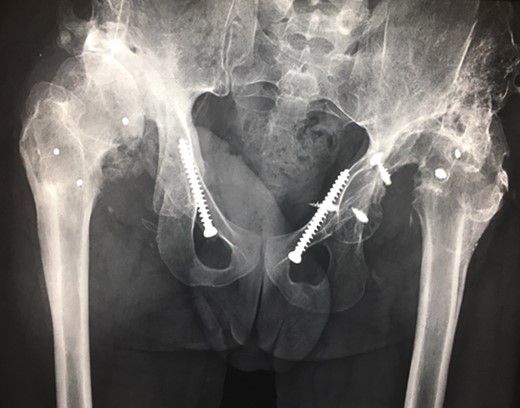

Ten years ago, a 12-year-old male presented to our clinic complaining about limping and massive swelling of the left hip. Figure 1 shows the initial X-ray and the 3D reconstruction of the left hip at first presentation when the femoral head, had already destroyed the lateral edge of the acetabulum like a mortar. Severe pain episodes have apparently not been noticed and a former hip dysplasia was not known. A brief clinical history revealed that the patient presented repeated episodes of finger biting and fevers from 2 to 8 years old. The intelligence level of the patient was at an average. The patient was admitted to a paediatric neurologist and a genetic test. A mutation of the NTRK1 gene was found and the diagnosis of CIPA was established. The right hip initially appeared to be normal and the patient was walking, therefore surgical reconstruction for the left hip was proposed due to massive swelling, inability of normal walking and significant limb length discrepancy. A Tönnis/Kalchschmidt triple pelvic osteotomy with open reduction and a shortening varus derotation osteotomy (VDRO) of the femur was performed (Fig. 2A–B). After 3 months the patient was walking again but another 3 months later the hip dislocated again without severe pain. Although the femoral head was already damaged the hip joint was reconstructed again by open reduction, capsular reconstruction with suture anchors and a trevira tube and a movable external fixator was used to temporary stabilize the joint (Fig. 3). The right hip at this time was still intact and was protected with a pneumatic orthotic device. A few months later in 2009, despite all surgeries, the left hip had entirely lost congruency and the right hip developed subluxation despite conservative treatment (Fig. 4). The patient was still walking so the decision to reconstruct the right hip with open reduction, capsular augmentation with a trevira tube, a triple pelvic osteotomy and VDRO was made (Fig. 5). Few months later this reconstruction failed as well and the hip dislocated without severe pain (Fig. 6).

(A + B): (2008) (A) Hip reconstruction with open reduction, Tönnis triple pelvic osteotomy and shortening rotational varus osteotomy of the left femur demonstrating correct deep reposition in ap view. (B) Lauenstein view shows that the acetabular congruency over the femoral head is restored.